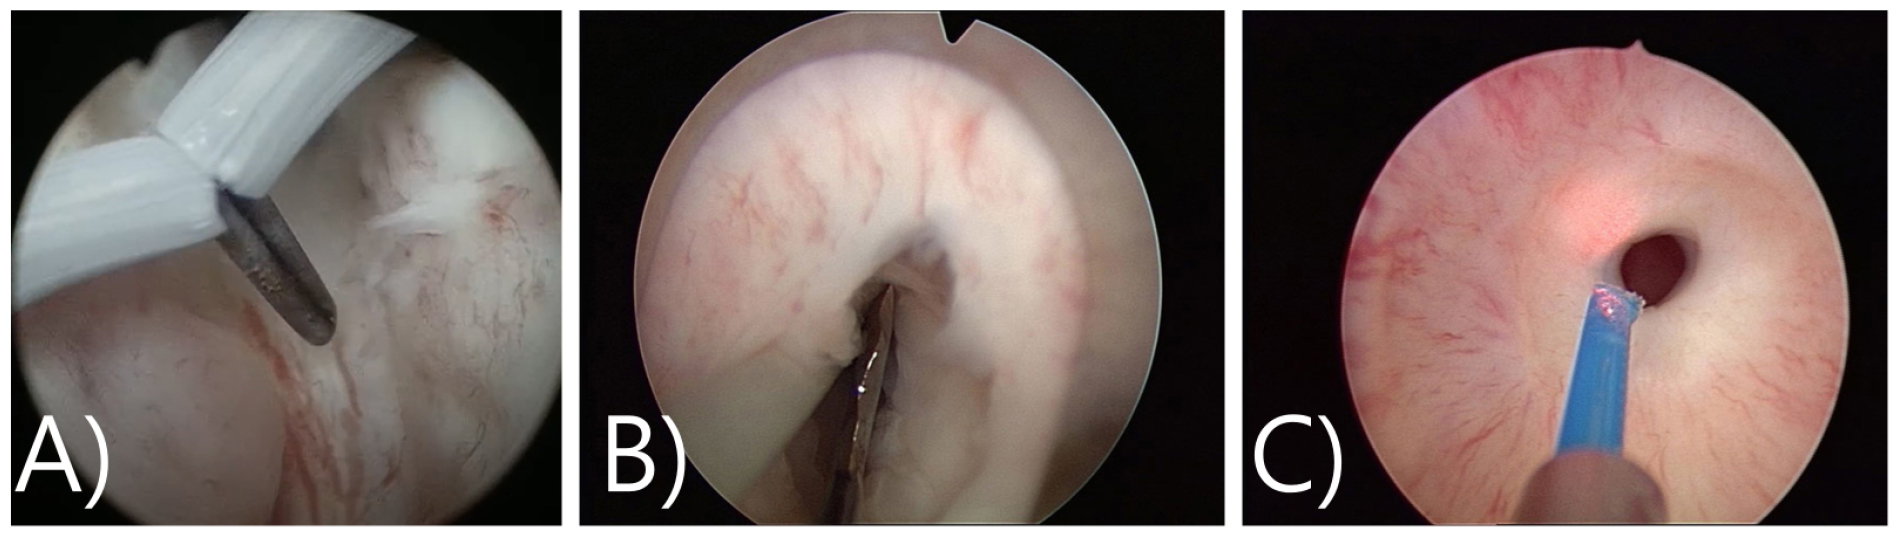

A) 65/M, TURP 후 방광목 협착(TRUS: 50 cc), 수술 3개월후 약뇨 소견으로 내원하여 시행한 내시경소견에서 얇은 막이 낀 방광목 협착이 확인되었으며, Flexible cystoscope이 진입이 안됨, sound dilation 시행하고 한달 후 2nd TURP 및 BNI를 시행함

B) 71/M, TURP 시행 후 발생한 방광목 협착- 진단(수술 9개월 후 진단) Prostate fossa가 넓어져 있고 pale 한 양상의 방광목 폐색을 야기하는 섬유화된 병변이 확인됨 (출처: 고려대학교안산병원 비뇨의학과)

C) 60/M, Holep 후 방광목 협착(TRUS: 16 cc), sound dilation 2차례기왕력이 있는 환자로 Prostate fossa가 넓어져 있으며, 협착부위에 calcification이 심하여 출구의 확인이 어려움 (출처: 서울탑비뇨의학과의원)